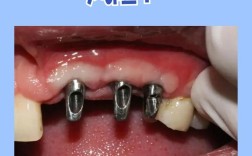

种植体(人工牙根)需要植入牙槽骨中,就像树木需要扎根在土壤里一样,牙槽骨的高度、宽度和密度直接决定了种植体能否稳固植入并长期承受咀嚼力。

- 种植体植入困难或失败: 没有足够的骨支撑,种植体可能无法获得初期稳定性,或者植入位置不佳,影响上部假牙的修复。

- 功能受限: 骨量严重不足时,即使勉强植入,也可能无法承受正常的咀嚼力,容易松动或折断。

现代口腔种植技术已经非常成熟,针对骨量不足有多种成熟的解决方案,核心思路就是增加骨量,也就是骨增量/骨增量手术,这就像在种植前先为种植体“搭积木”,创造一个稳固的基础。